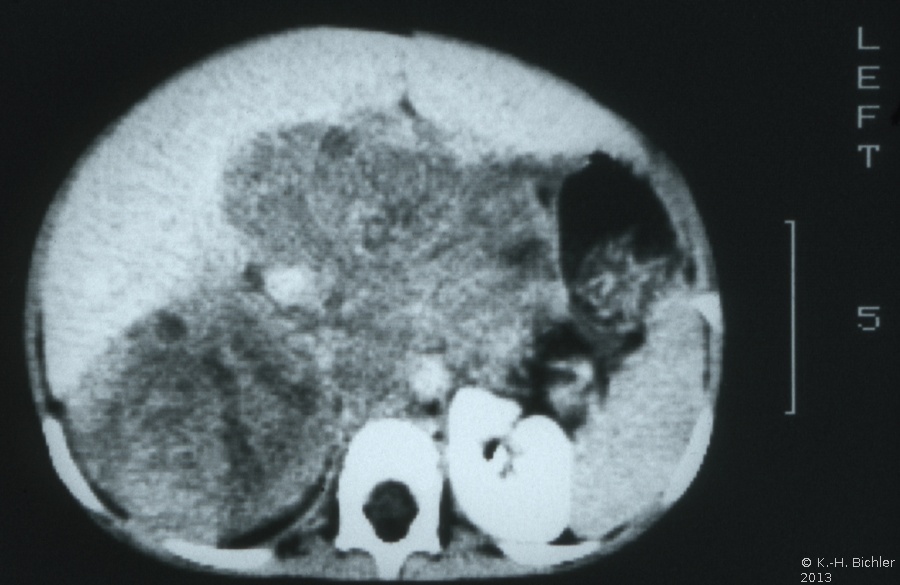

Die Computertomographie zur Bestimmung der Tumorausdehnung, zum Ausschluss einer zystischen Nierenfehlbildung (Differentialdiagnose) und zur Suche nach einem eventuellen kontralateralen Nierentumorbefall von Interesse. Außerdem dient das CT zur Flankierung der Chemotherapie (Ergebniskontrolle) (Abbildung 7,8,9).

(Die Abbildungen 7-8 wurden uns freundlicherweise von Herrn Dr. med. Günter Antes, Kempten überlassen)